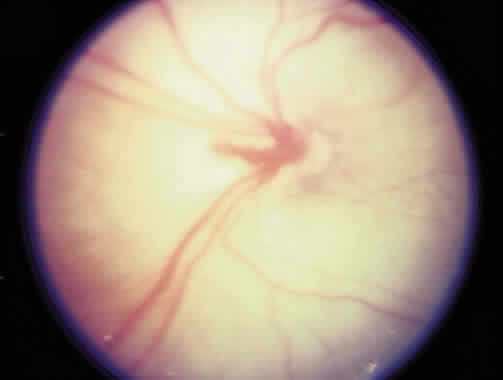

The most common form of regression of ROP is continued growth of the retinal vasculature anteriorly with gradual fading of the disease at the border of posterior vascularized and anterior avascular retina. Another more dramatic sign of regression is the growth of vessels beyond the ridge (Fig. 1). The vessels penetrate into the avascular retina as an arteriole with an accompanying venule. As the vessels grow beyond the ridge, the dilation and tortuosity of vessels just posterior to the shunt and in the posterior pole diminish.

Fig. 1. Regressing retinopathy of prematurity. The vessels have crossed the ridge and are growing into the avascular zone.